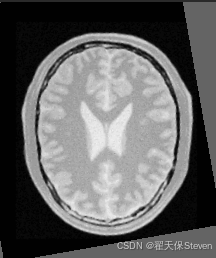

测试效果

官方给定的浮动图像在 X 轴方向偏移了 13 像素,Y 轴方向偏移了 17 像素,并旋转了10度,理想情况下配准结果应该接近这三个值。在实际运行中,优化器会找到最优的变换参数,输出类似如下的结果:

从结果可以看出,配准得到的平移量非常接近真实偏移量,说明配准算法成功地找到了最优变换参数。但也能看出仍存在一定位移偏差,官方也给出了解释,因为配准示例中采用了质心对齐的方法,而人为创造偏差时并不是这样处理的,所以整体的平移会有偏差。

过程图像如下:

配准后图像